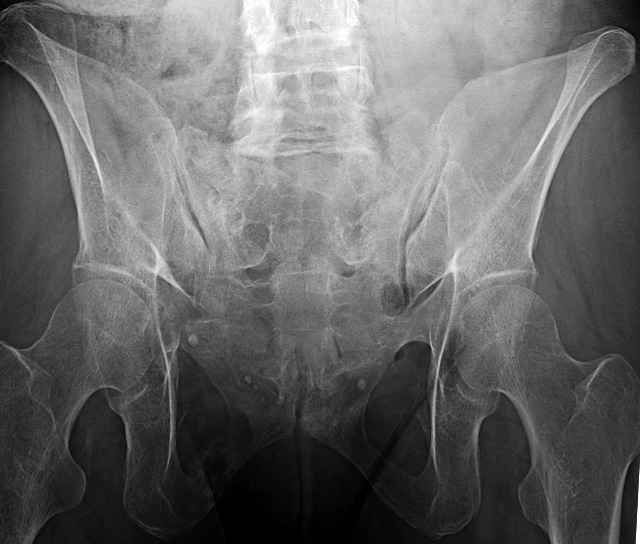

hello everyone, attached are images of a 59 yo female, admitted today after motor vehicle collision. Pt states her pelvis has been very painful ever since she fell on her buttocks from ground level a little over a year ago. medical history significant for scleroderma, raynauds syndrome, and COPD. no past surgeries.

pt states she is very limited in walking ability secondary to pain. she requires a cane or a walker. friends and family do her shopping. the pain is localized primarily around left upper groin. she points to the rami region.

I’ve operated on 30-35 similar symptomatic patients... usually females in that same age range and most with prior trauma and then with sustained chronic activity related pain due to presumed insufficient healing and resultant ring instability (enough to hurt but not displace too much)...almost all have xray evidence of most of us would consider “hypertrophic” ramus nonunions, and most all have some form of sacral or other posterior ring corresponding injury.

Here are a recent patient’s example slides...

54 yo Female Fell c/o Pain

Initial Films

?Instability on Exam - Limited by Pain

NonOp Initial Mgmt

3 Months After Fall

Continued Pain & Immobility

(+) Instability to Compressive Manual Exam

Pelvic CT Scan - 3 Months After Fall

Sacral Injuries

Ramus Fractures